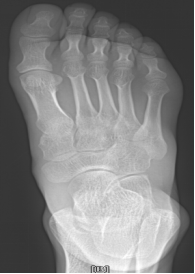

痛风

嘌呤代谢紊乱,以体液、血液中尿酸增加及尿酸盐沉着于各种间叶组织内引起炎症反应

好发于男性,发病高峰40-60岁

以第1跖趾关节最为多见

早期周围软组织肿胀,出现局限骨质硬化,晚期关节面边缘出现囊状、穿凿状骨质缺损,关节间隙可变窄,关节面不光整,晚期骨赘形成可使骨端增大

75Y,M